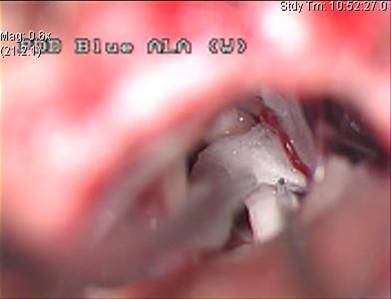

Trigeminusneuralgie is een zeer dynamisch proces,wanneer dit bekeken wordt onder een electronenmicroscoop, zien we dat een trigeminuszenuw van patienten met trigeminusneuralgie abnormaliteiten vertonen, zowel in de axonen van de zenuw (dit is het deel van de zenuwvezel die de impulsen doorstuurt) en in de myeline (dit is de beschermende laag die rond de zenuwen ligt).

De axonen kunnen stervende zijn, ze kunnen dood zijn of ze kunnen opnieuw aan het groeien zijn.

De myeline kan enkele lacunes vertonen of kan volledig verdwenen zijn, op bepaalde plaatsen waar de beschermende laag van de myeline verdwenen is, kunnen twee naakte axonen elkaar aanraken. Er zijn dus twee processen aan de gang : eerst is er een bloedvat dat klopt op de zenuw, en een heel klein percentage van de gevallen kan de pijn veroorzaakt worden door een plaque van multiple sclerose.